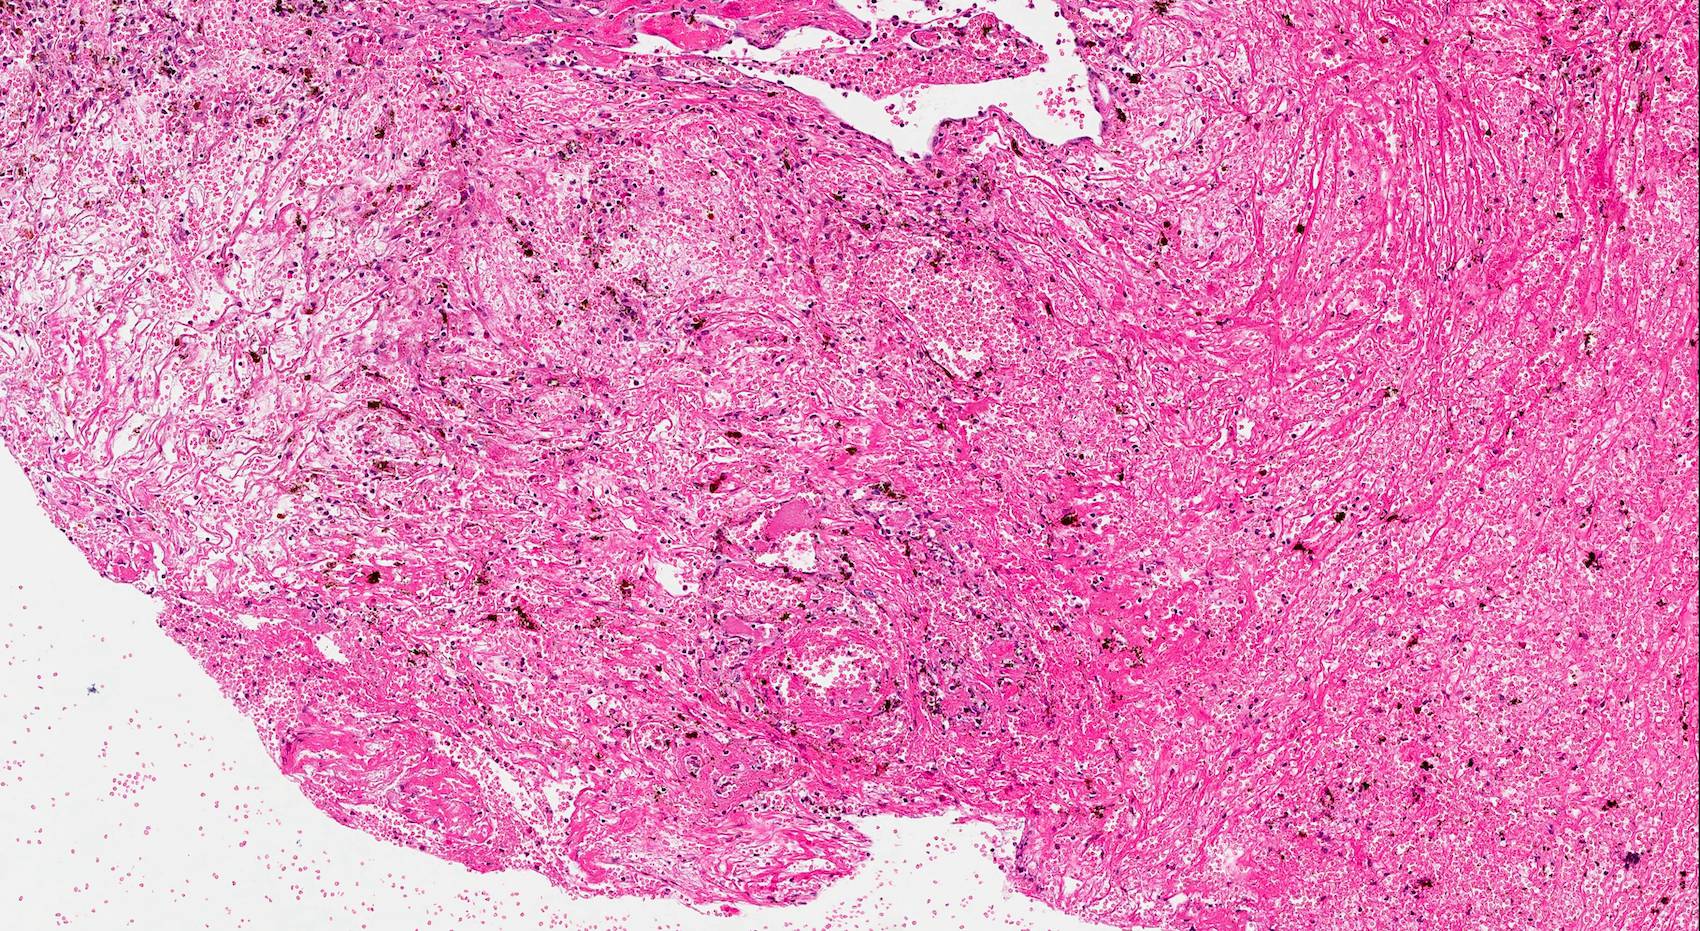

Microscopic (histologic) description

- Edematous, fibrotic or loosely myxoid stroma covered by respiratory epithelium

- Infiltrated by mixed inflammatory cells, including lymphocytes, plasma cells, eosinophils, neutrophils and mast cells

- Surface epithelium can show ulceration or squamous metaplasia

- May have bizarre stromal cells (large and pleomorphic)

- Submucosal glands are decreased or absent

- Concurrent fungal infection may be seen

- Rarely, osseous metaplasia may be present

Microscopic (histologic) images